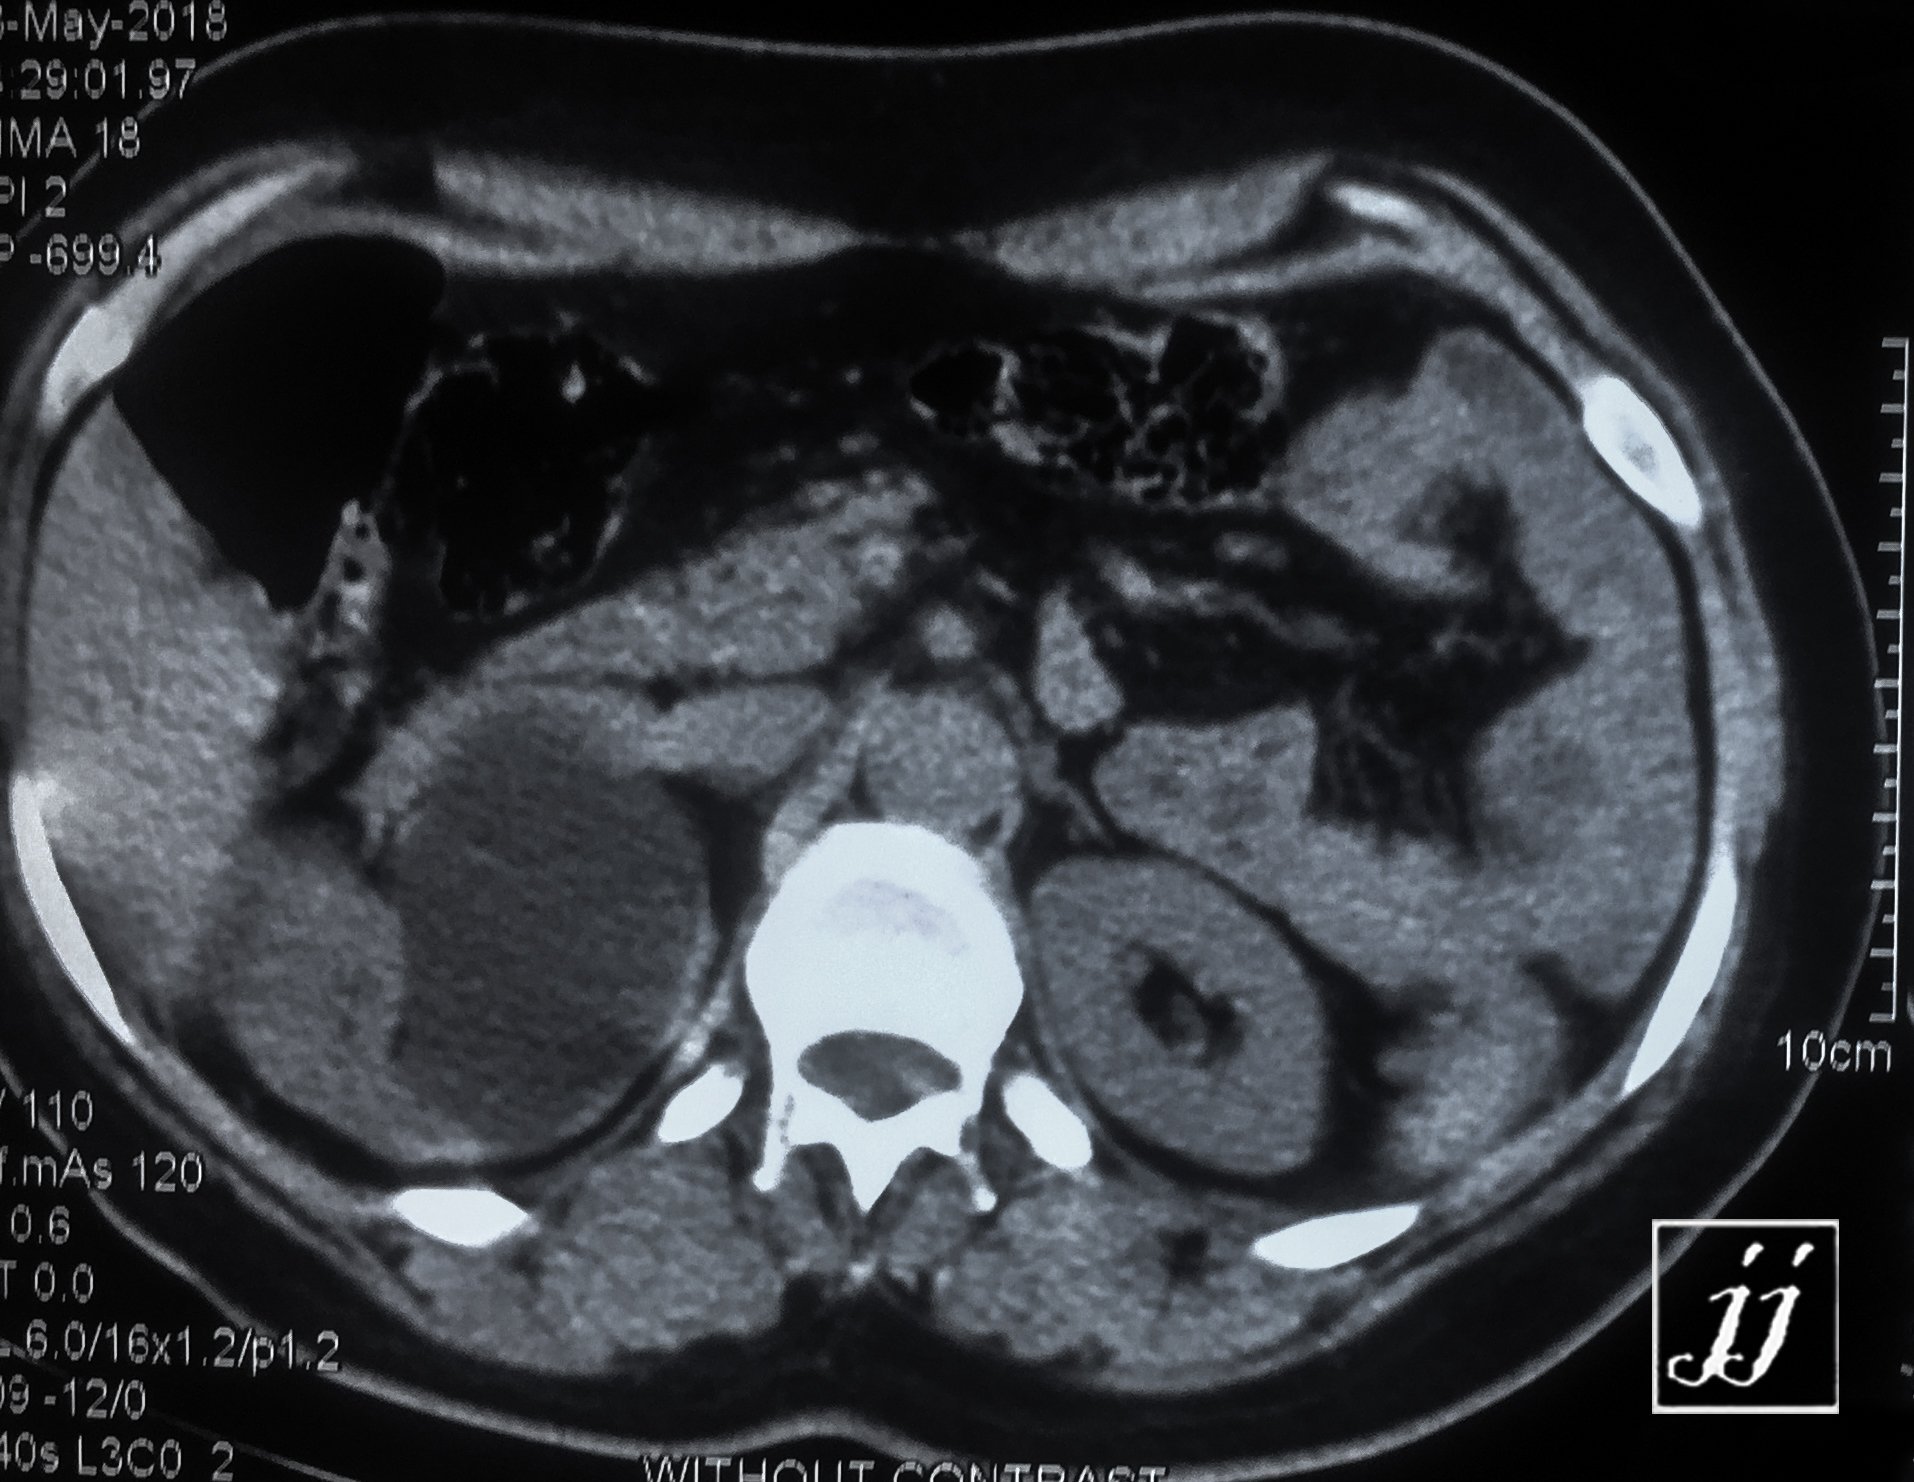

Abdomen- right side severe hydronephrosis and ureter (23)